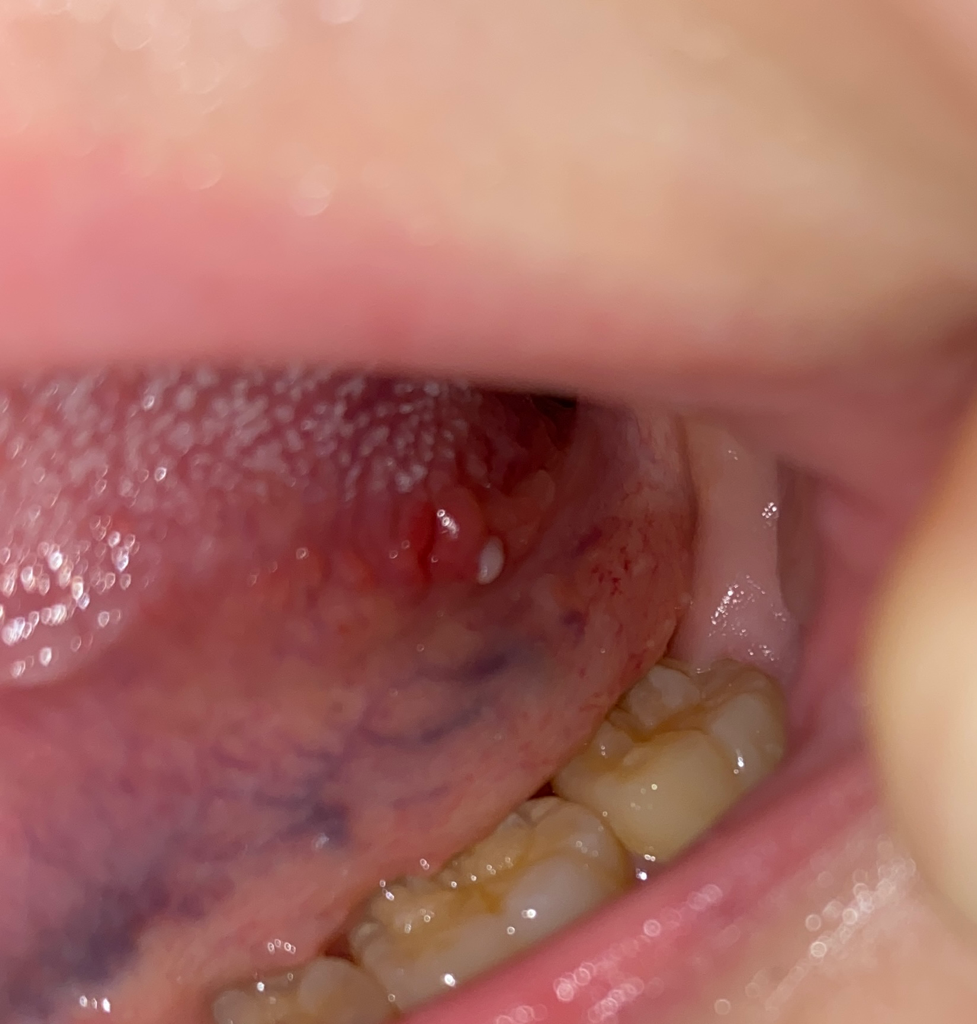

설암 발병 위치와 동일해서 너무 걱정됩니다 설암인가요?

설암 발병 위치인 혀뿌리쪽 측면에 동그란 붓기와 하얀 돌기? 같은게 났습니다. 혹시 사진상으로 설암으로 보이나요? 아님 단순 구내염 일까요..

현재 사진상으로는 구내염으로 판단이 되나, 만약 계속 없어지지 않고 크기가커지는경우에는 보다 정확한 상태 확인을 위해 치과 진료를 받길 권합니다.

사진으로만 봤을 경우에는 단순한 구내염으로 보입니다.

설암은 아니신거 같습니다 그렇게 걱정이 되신다면 대학병원 구강내과나 구강외과를 가보시는걸 추천드립니다.

구내염이 낫고 있는 상태로 보입니다. 구내염은 처음 생기고 1~2주면 자연스럽게 회복됩니다

조금 더 증상을 지켜본 뒤 계속 사라지지 않으면 그때 병원을 가보셔도 될 것 같습니다

현재로서는 악성병소의 가능성은 높지 않습니다.

악성병소는 흔히 자발적인 출혈을 일으키고, 경결감(만졌을 때 딱딱한 느낌), 불규칙한 외형을 보입니다